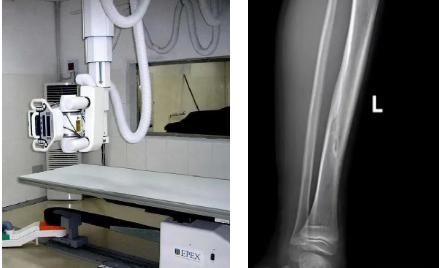

1.定期復(fù)查。一般于骨折后2-4周,骨折進(jìn)入骨痂期,骨折斷端有新生骨形成,呈明顯高密度,無(wú)論是X線或是CT,都能比較清晰觀察到,通過(guò)前后圖像對(duì)比,較容易診斷隱匿性骨折。